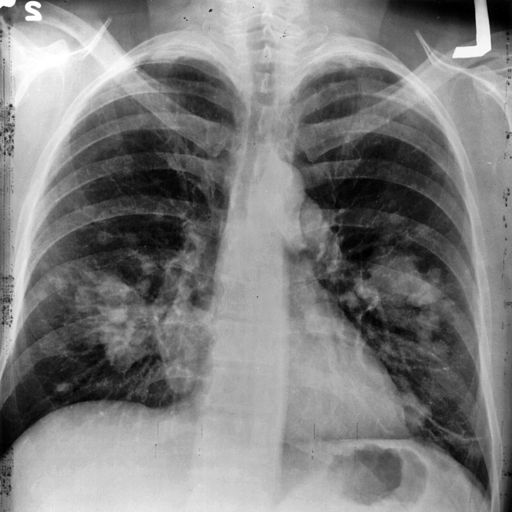

The Annals of Internal Medicine produced a hat-trick of material on screening for lung cancer, a study, a letter, and editorial. What is the big interest?

The National Lung Screening Trial demonstrated a 20% reduction in lung cancer deaths when persons were screened with low dose computed tomography (a more sensitive test) versus a plain X-ray. This study along with other evidence formed the current national guidelines from the US Preventative Services Task Force (USPSTF).